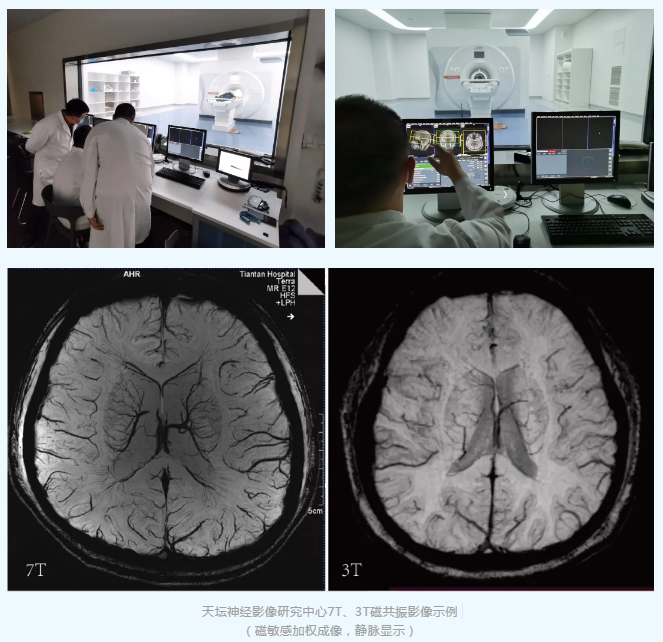

7T超高场磁共振是目前可用于人体扫描的先进磁共振成像系统,相比于传统1.5T和3T的磁共振,7T磁共振可以提供倍增的信噪比、更精细的空间分辨率、更优异的组织对比度,更加适合观测组织的精细结构和功能代谢生理变化等信息,从而揭示传统平台难以发现的生理病理机制;例如,传统3T影像扫描下难以观测的穿支动脉和微小静脉可以在7T磁共振扫描下清晰成像,这为脑血管病及其他神经系统疾病的精准诊疗提供重要的影像学依据。7T磁共振将成为天坛神经影像研究中心开展高水平脑科学研究和神经系统疾病临床研究的重要工具。

天坛神经影像研究中心目前已启用国际顶级的7T超高场磁共振MAGNETOM Terra、3T磁共振MAGNETOM Prisma和SIGNA Premier等多台先进科研磁共振影像设备,承担前沿临床研究的影像学方案设计、技术开发、流程管理、数据采集和数据分析等任务,同时中心与国际一流研究机构合作开发影像新技术和后处理解决方案,积极开展人工智能和大数据影像分析的创新工作,研究成果丰硕。